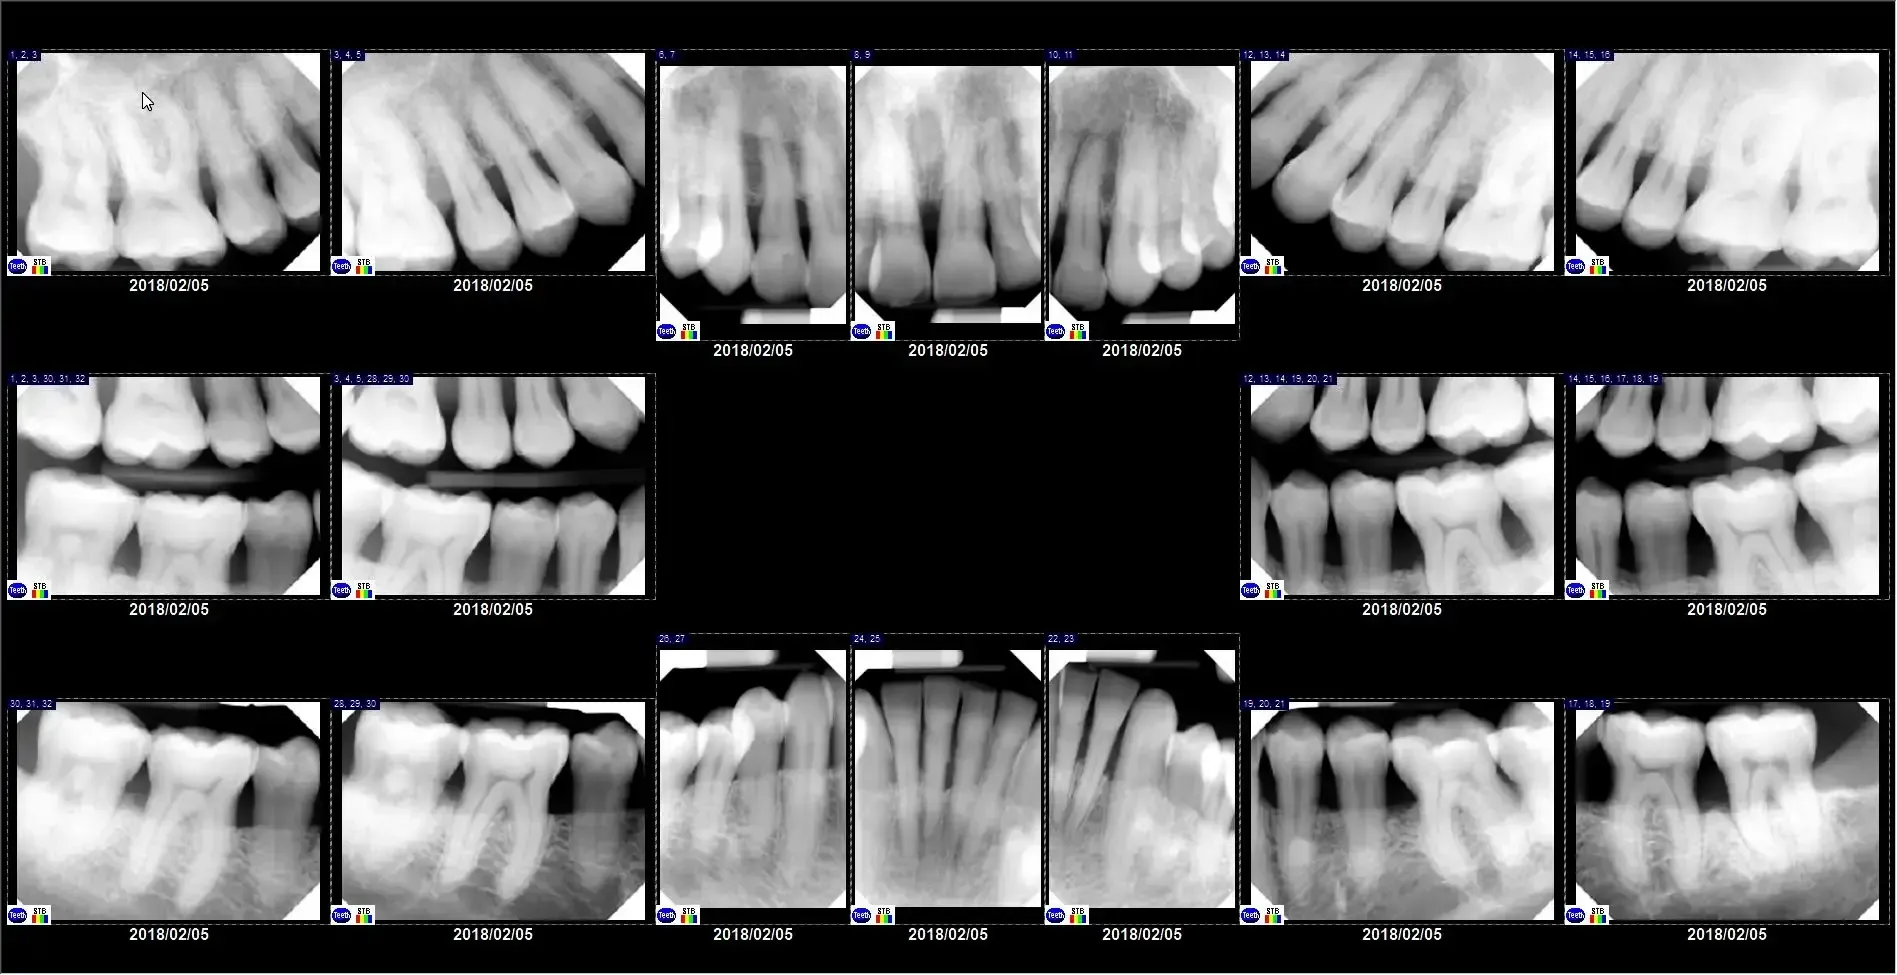

Bitewing X-rays

These x-rays of the back teeth are usually taken in groups of 2 or 4, so 1 or 2 per side. Sometimes it may be a group of 7 in a different orientation. Most people have get them every 12 months to check for cavities between the teeth, where we can’t see them. If you’ve never had a cavity between your teeth and are at low risk, your dentist might change it to every 18-, 24-, or rarely every 36 months. Or if you get cavities a lot, your dentist might even recommend them every 6 months. The patient in the below example has gotten a mouthful of dental crowns in her 70+ years. Because we want to catch any cavities around the crowns early, she definitely gets bitewings once a year.

Full-Mouth Series

For patients who have cavities on many teeth, or especially if they have gum (periodontal) disease , we take a full-mouth series of x-rays. This is a minimum of 10 total x-rays, including both bitewings and periapical dental x-rays.